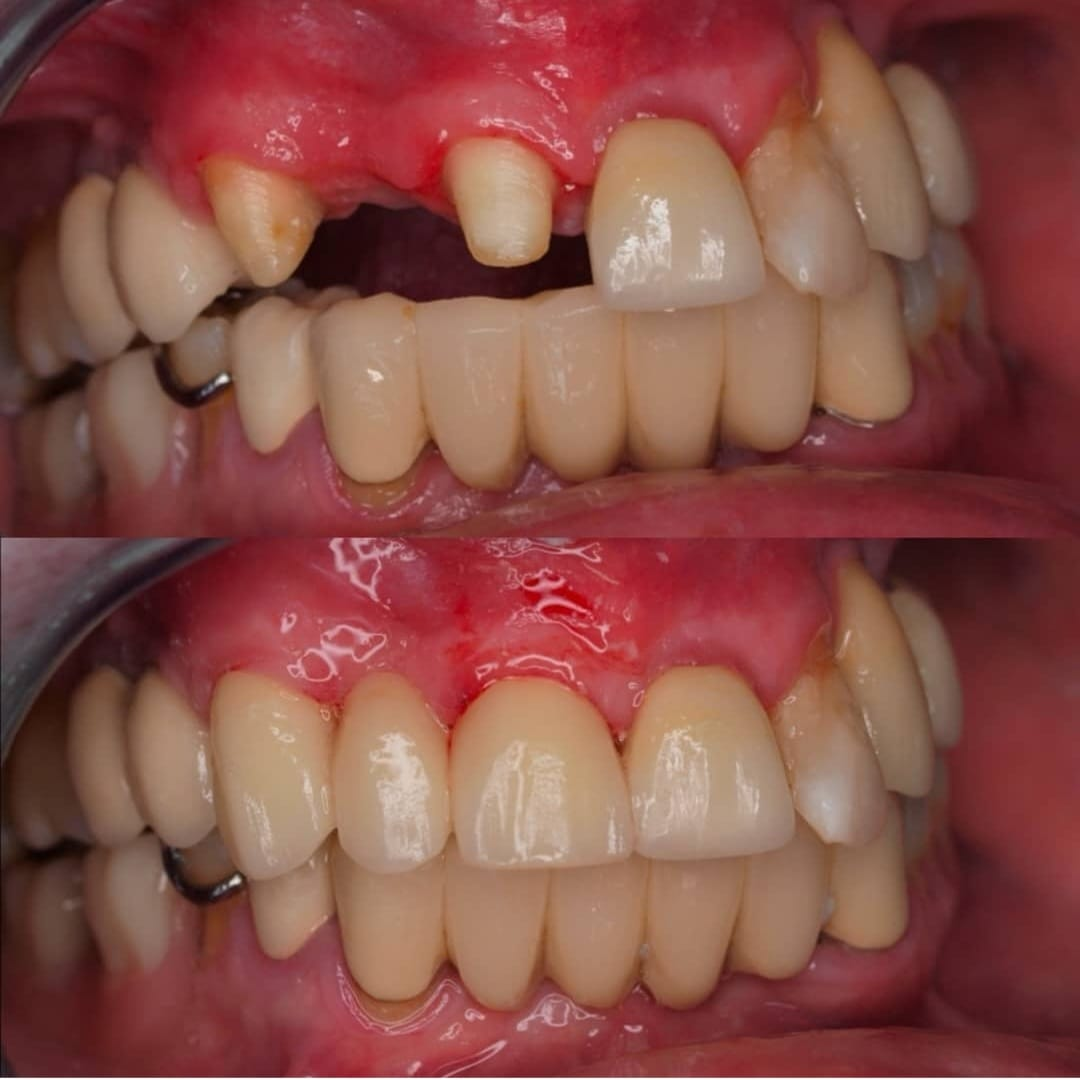

Casos de pacientes

En Clínica Dental Dr. Molinete trabajamos para que los procesos y las intervenciones sean lo más rápido y eficaz posible y con el mejor de los tratos. Tras 12 años de experiencia contamos con diferentes casos de pacientes resueltos de forma óptima.